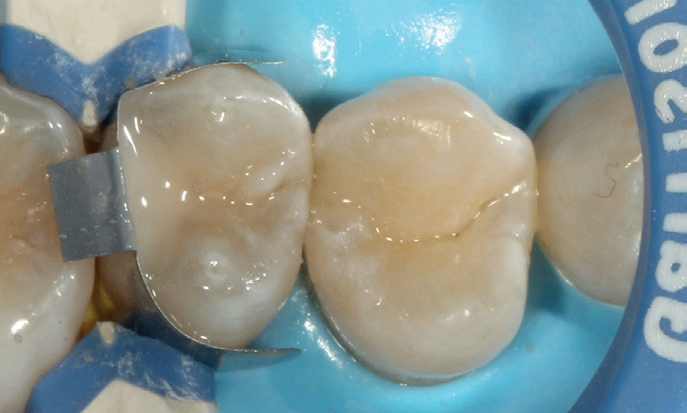

Figure 8: Single increment of Stela up to the cavity margins

Figure 9: Appearance after four minutes fully set